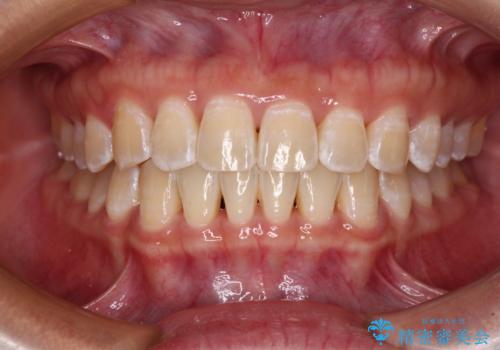

前歯の隙間と上下正中のズレを解消

正中がなかなか合わずに、2年近くの治療期間を要しました。